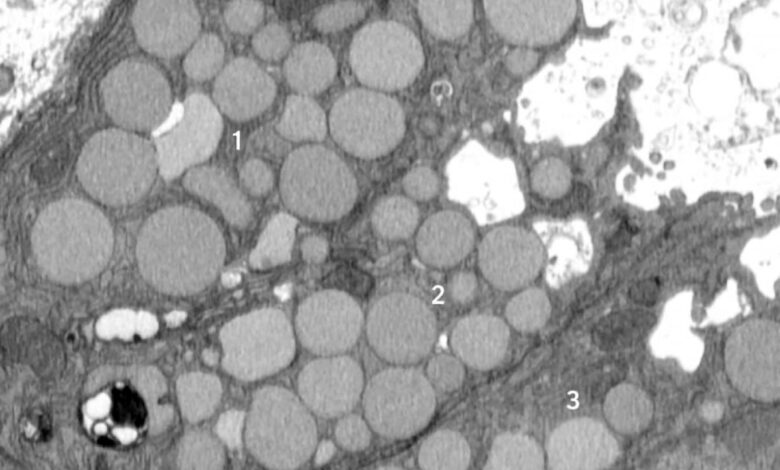

Kromě známých procesů, jako je programovaná buněčná smrt a kontrolovaná recyklace, vědci zjistili, že buňky mohou najednou „zvracet“ své vnitřní stroje a čistí se, aby se resetovaly do stavu podobného kmenovým buňkám. Tato zkratka, nazývaná katartocytóza, urychluje regeneraci, ale zanechává odpad, který může podnítit chronický zánět a rakovinu.

Brown porovnával katartocytózu s „zvratem“ buněčným odpadem, zkratkou, která umožňuje buňce vyčistit nepořádek a soustředit se na přestavbu tkáně rychleji, než by mohla prostřednictvím pomalejšího, krok za krokem rozpadu odpadu.

Při paligenóze se poškozené buňky posunuly od jejich normálních rolí a podstoupily proces přeprogramování do nezralého stavu a chovaly se jako rychle dělící kmenové buňky, jako se to děje během vývoje. Původně vědci předpokládali, že k poklesu buněčného aparátu v rámci přípravy na toto přeprogramování dochází zcela uvnitř buněčných kompartmentů zvaných lysosomy, kde se odpad trápí pomalým a obsaženým procesem.

Od začátku však vědci všimli trosek mimo buňky. Zpočátku to odmítli jako nedůležité, ale čím více vnější odpad, který viděli ve svých raných studiích, začalo Browna mít podezření, že se děje něco úmyslného. Použil model poškození žaludku myši, který spustil přeprogramování zralých buněk do stavu kmenových buněk najednou, což zřejmé, že „zvracení“ odezva – nyní se odehrává ve všech žaludečních buňkách současně – byla rysem paligenózy, nikoli chyby. Jinými slovy, proces zvracení nebyl jen náhodným únikem sem a tam, ale nově identifikované standardní způsob, jakým se buňky chovaly v reakci na zranění.